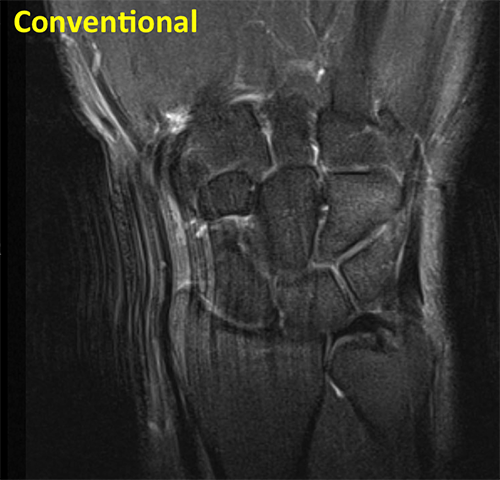

Wrist Conventional

Conventional coronal fluid sensitive sequence of the wrist shows intermediate signal of articular cartilage, and low signal in the triangular fibrocartilage (TFC).